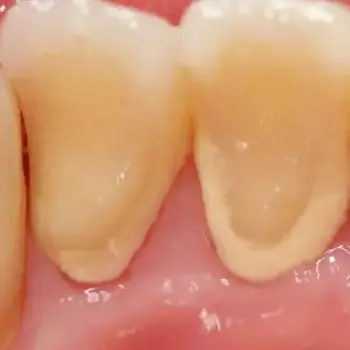

치석은 일 년에 1~2번 정도, 정기적으로 치과를 방문하여 치과 의사의 케어를 받는 것이 좋습니다. 치석 제거는 초음파 또는 치과 전용 치석 제거기 등으로 세세한 부분까지 케어하게 됩니다.

이런 치석제거의 스케일링은 건강보험으로 처리가 가능하니 비용은 그다지 걱정하지 않아도 됩니다.

치석이 없는 건강한 구강 내 환경을 유지하려면, 치석의 원인이 되는 플라크를 올바른 칫솔질로 매일 제거해 주는 것이 좋으며 일 년에 1~2회 정도는 시간을 내어 치과에 방문하여 구강 케어를 받는 것이 좋습니다.